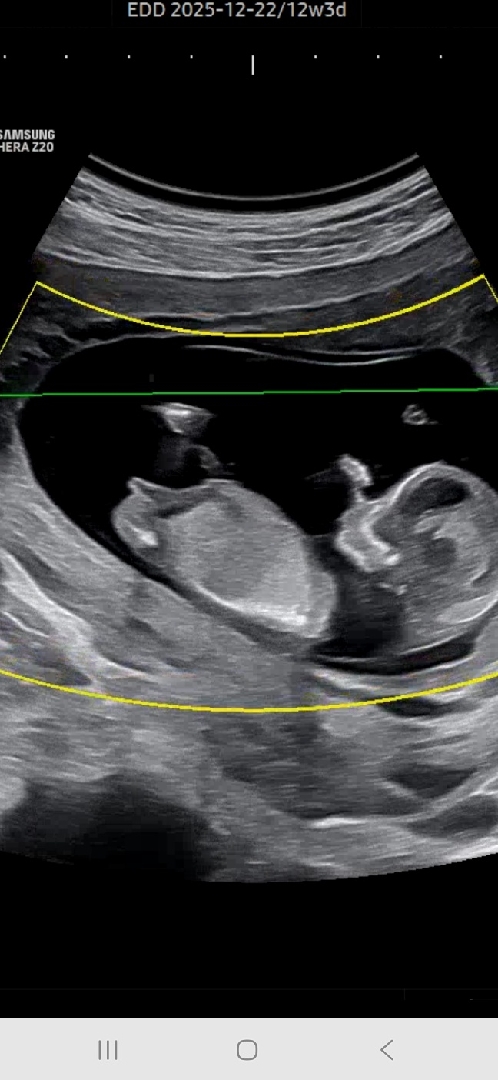

초음파 아들,딸???일까요..

12주인데 선생님이 아직 잘 모른다구.. 있다가도 안보일수도 보이다가도 안보일수있다며.. 16주나되야 보인다네요ㅜㅜ 혹시 어떻게 보이시나요?!

각도는 딸같은데 전왠지 아들일거같아요 ㅋㅋ

저두 딸에 한표요!!

딸 각도 같아요.